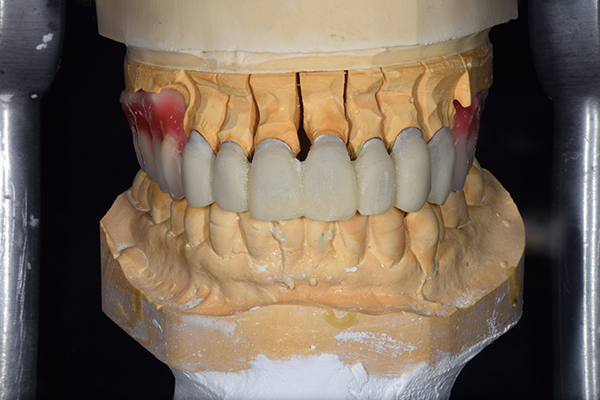

7.歯を並べる

噛み合わせをが決定したら、咬合器という装置に模型をくっつけて、歯を並べていきます。自費の入れ歯の場合こちらを歯科医師で行います。保険の入れ歯の場合は模型を技工所に送り、技工士さんに歯を並べてもらいます。最終的な入れ歯を作る気持ちで並べていきますが、どうしても噛み合わせの誤差が模型とお口の中とでは生じてしまいますので、歯をならべたものを患者様のお口の中にいれて確認していきます。

確認することとしては、歯と患者様のお顔の調和、噛み合わせ、見た目、フィット感などです。 こうすることで、患者様に合った精密な入れ歯を作ることができます。

8.患者様のお口に入れて修正

この写真は、実際にお口の中にいれてみて、噛み合わせのチェックを行い、調整したものになります。 上下の入れ歯で青い点、赤い点がはっきりあり、これはしっかり奥歯で噛めるというサインになります。 また、入れ歯自体の大きさや、違和感が強くないか、お顔と調和しているか、唇との関係などをみていきます。もし、ここで大きな修正が発生する場合はもう一度お時間をもらって次回再度確認させて頂きます。 これで修正が終わったら、その模型を技工所に送り、入れ歯を完成させてもらいます。